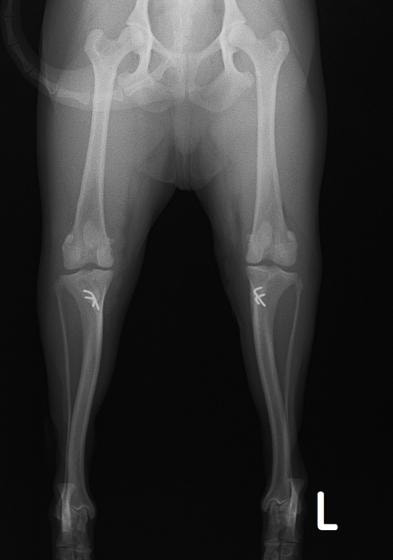

■ 症例22 ポメラニアン 1歳5か月 去勢雄

左後肢の挙上を主訴に来院した。整形学的検査、レントゲン検査より左右の膝蓋骨脱臼(左GradeⅡ〜Ⅲ、右Grade Ⅱ)を認めた。また、脛骨の前方引き出し試験の際に、引き出し兆候は認められないものの、疼痛が認められたため、前十字靭帯の損傷が疑われた。術中における、目視および関節内の操作によって、前十字靭帯の損傷や過伸展といった異常が認められなかったため、膝蓋骨脱臼の整復のみ実施した。手術手技は縫工筋及び内側広筋の解放、脛骨粗面の外側転位、滑車ブロック形造溝術、内外側関節包の縫縮を実施した。本症例は跛行もなく経過良好である。しかし、頸骨高平部の角度(TPA)が 右26.2°、左24.9°であり、解剖学的に前十字靭帯損傷のリスクが高いことから今後の経過に注意が必要である。